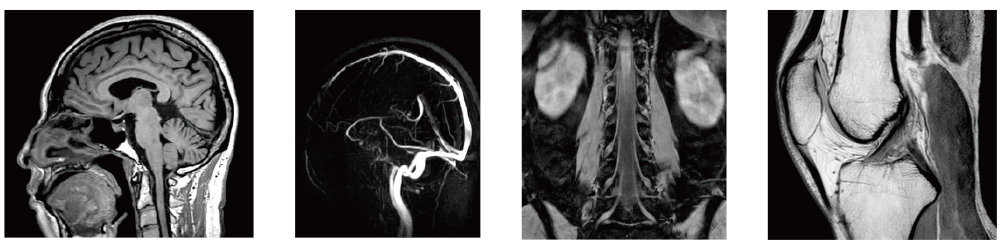

AutoPose Cardiac GUI

AutoPose FemalePelvis

AutoPose Knee

A technology to convert extensive CT data accumulated through SYNAPSE 3D into MRI images utilizing AI technology has been developed. This technology, combined with a convolutional neural network (CNN) library established during the development of organ segmentation, has been utilized in the development of MRI positioning. As a result, highly accurate positioning capabilities have been commercialized for numerous anatomical regions.

The slice line setting support function, "AutoPose," automatically sets the slice lines as soon as the scanogram is scanned.

After the completion of MRA imaging, it automatically performs clipping for cerebral MRA. The automatic clipping identifies the extraction range based on the characteristics of the head. Additional clipping can also be performed on the images after the automatic clipping process.